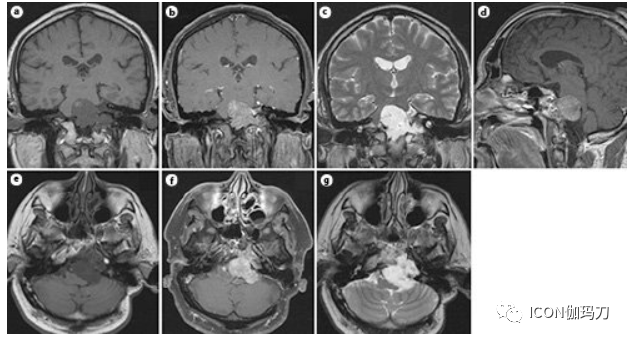

图3.颅内软骨肉瘤的MRI扫描。冠状位(a, b)、矢状位(d)、轴位(e, f) T1加权和冠状位(c)、轴位(g) T2加权MR显示肿瘤向后颅窝扩展。b, e, g对比增强图像。